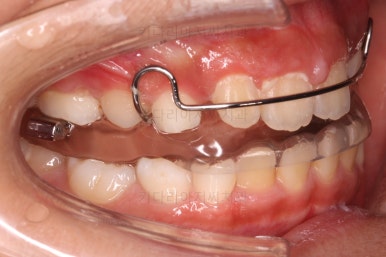

마찬가지로 초진시의 입안 모습입니다.

보호자분 말씀처럼 윗니가 아랫니에 비해서 나와보이는게 사실이네요.

이번 환자분은 무턱 + 돌출입 성장교정이 목표였지만 그전에 치아의 맹출경로가 엉켜서(화살표) 치아의 손상 혹은 매복치아의 우려가 있는 부분을 먼저 개선하기로 했습니다.

간단하게 장치를 부착하고 경로가 심하게 벗어나 있는 치아를 원위치로 당겨줍니다.

성장교정에 앞서 이러한 치아배열 작업을 약 5개월 정도 해주었어요.